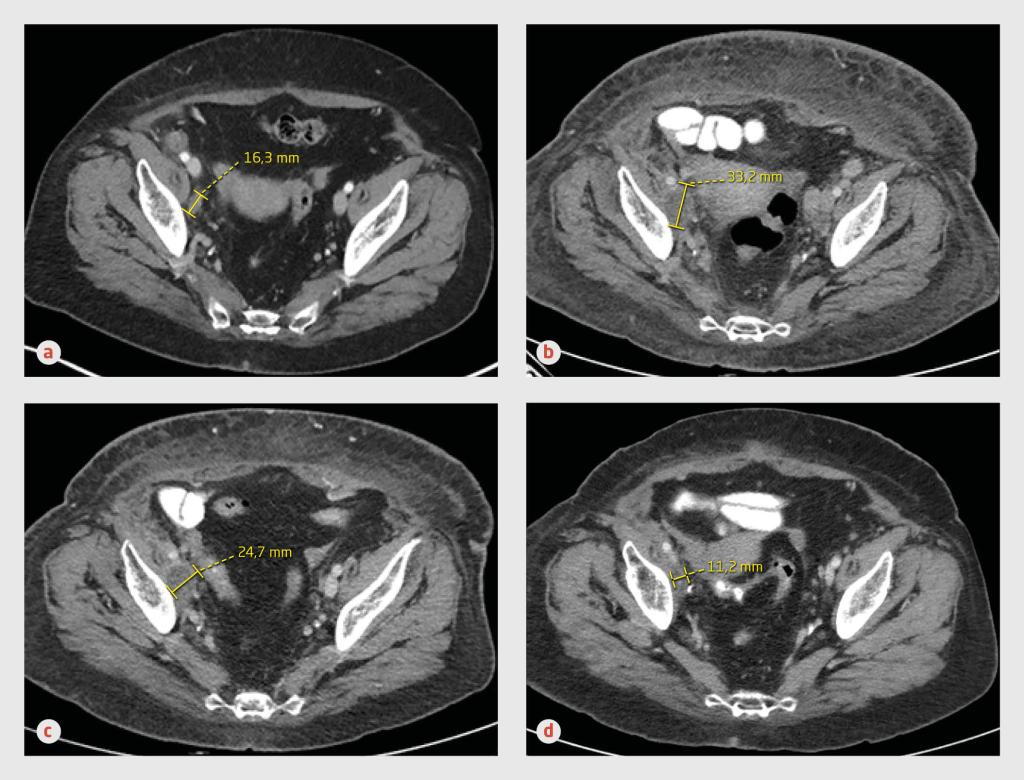

Figuur 1 | Pseudoprogressie bij patiënt A

Transversale CT-opnames van het abdomen van een 63-jarige vrouw met een lymfogeen en cutaan gemetastaseerd melanoom. (a) Op het moment dat gestart wordt met immuuntherapie met nivolumab is mediaal van het os ilium een pathologische lymfeklier met een diameter van 16 mm zichtbaar. (b) 6 maanden na aanvang van de immuuntherapie blijkt de lymfekliermetastase in grootte te zijn toegenomen. (c) 6 weken later is de lymfekliermetastase in grootte afgenomen. (d) 10 maanden na aanvang van de immuuntherapie is een complete remissie bereikt.

Bij responsevaluatie gedurende de opname namen de axillaire en intra-abdominale lymfekliermetastasen zowel in aantal als in grootte toe. De cutane metastase was echter wel afgenomen in grootte. Om die reden, maar ook omdat we geen aanwijzingen hadden voor een immuun-gemedieerde oorzaak van de decompensatio cordis, besloten wij de immuuntherapie te continueren.

6 weken later waren de lymfekliermetastasen fors in grootte afgenomen en na een behandelduur van 10 maanden was een complete remissie bereikt. Wij stopten de behandeling met nivolumab. Bij poliklinische controle 13 maanden nadat de immuuntherapie was gestopt, voelde patiënte zich uitstekend en waren…